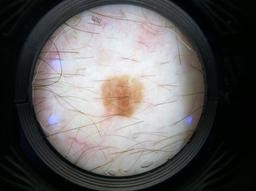

Biopsy-confirmed melanocytic and non-melanocytic skin lesions. This dataset includes over 500 melanomas. Many images have polarized and contact variants.